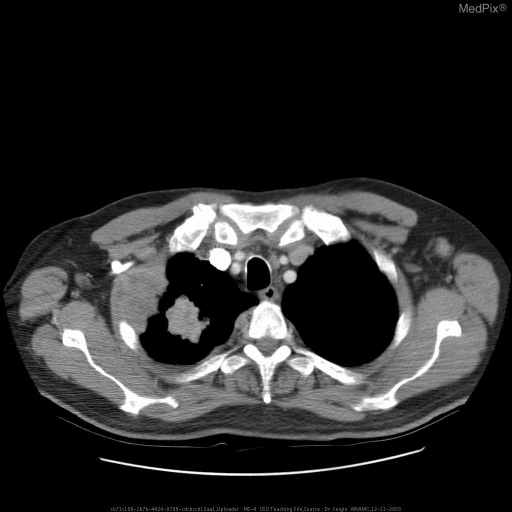

• Chest CT — first-line for all suspected cases; defines size, location, nodal involvement

CT showing right upper lobe spiculated mass consistent with bronchogenic carcinoma

Axial CT — spiculated right upper lobe mass, classic appearance of primary bronchogenic carcinoma